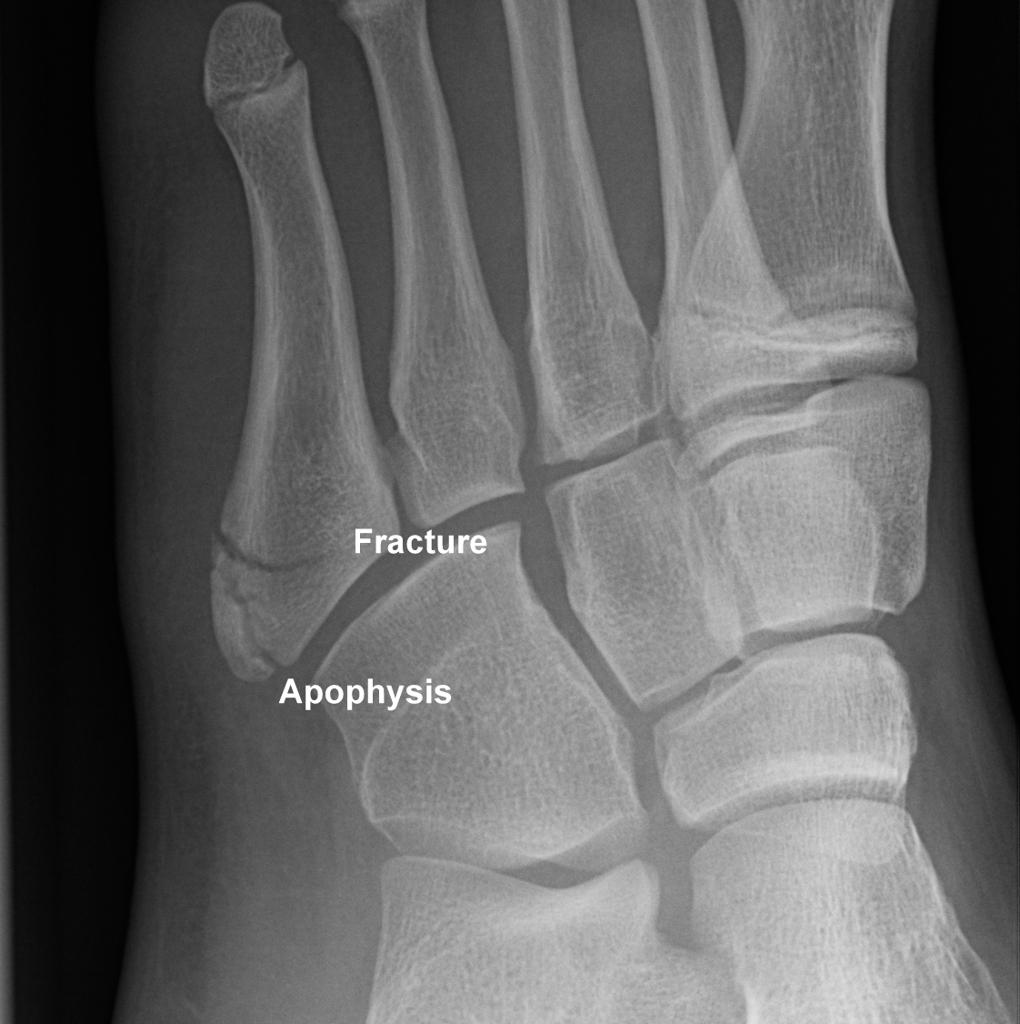

• apophysis of proximal 5th metatarsal

• oriented longitudinally parallel to the shaft

• important to differentiate from fracture, which is oriented transversely